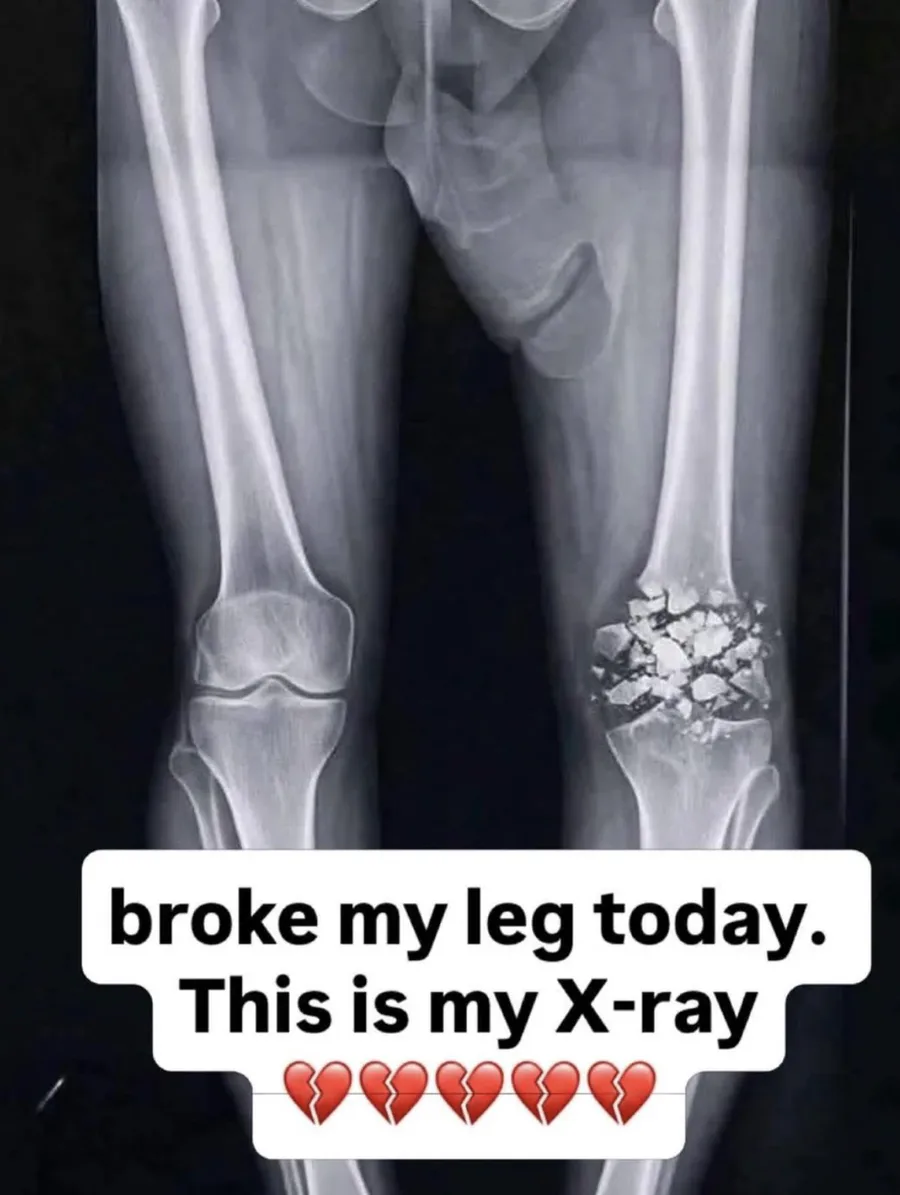

Pray for me 😔 🙏